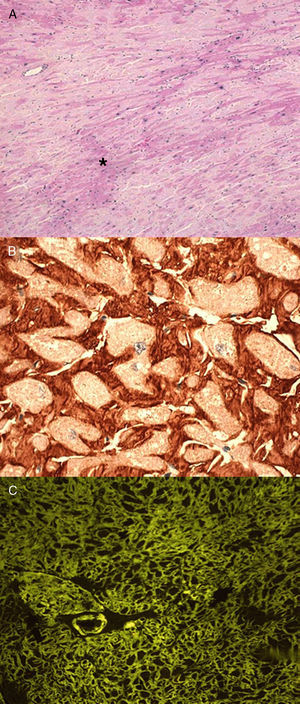

Anatomopatológicamente, los depósitos amiloides aparecen como material hialino que se tiñe con rojo Congo (dando refringencia verde bajo luz polarizada), tioflavina T (produciendo una intensa fluorescencia amarillo-verdosa) y azul Alcián (tinción verde) como se muestra en la Figura 12.

Figura 1. Biopsias cardiacas de paciente con amiloidosis cardiaca hereditaria por transtiretina. A: tinción de hematoxilina-eosina (×200); los depósitos de amiloide (*) aparecen como material amorfo entre los miocitos. B: inmunohistoquímica para detección de transtiretina (×400); depósitos color teja perimiocitarios. C: tinción de tioflavina T (×200); depósitos amarillo-verdosos situados alrededor de los miocitos que se corresponden con depósitos de sustancia amiloide. Modificado de García-Pavía et al 2 , cortesía de la Dra. C. Salas, del Hospital Universitario Puerta de Hierro, Madrid, España.